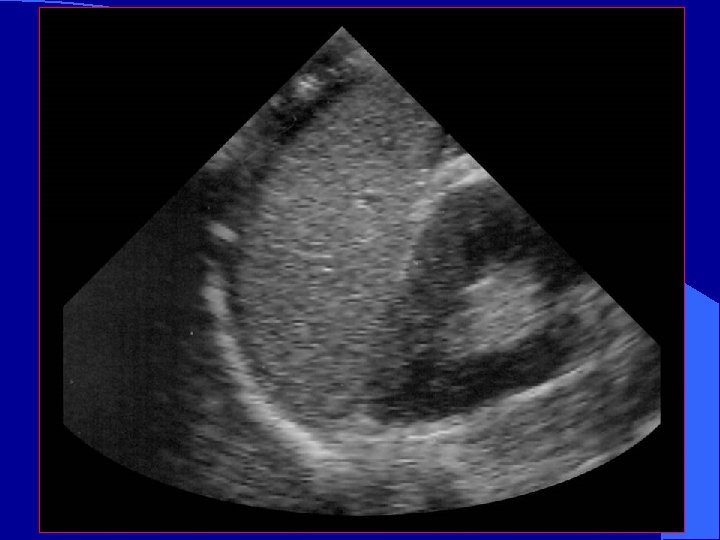

RUQ l Image on screen: – Liver cephalad – Kidney inferiorly – Morison’s Pouch*: space between Glisson’s capsule and Gerota’s fascia * *

Normal RUQ l Image kidney – Longitudinally – Transversely l Two toned structure – Cortex/medulla – Renal sinus

Appearance of blood l Fresh blood – Anechoic (black) l Coagulating blood – First hypoechoic – Later hyperechoic

Normal Morison’s Pouch Free fluid in Morison’s Pouch